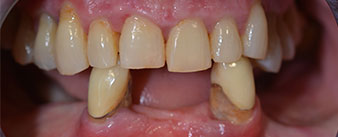

La patiente âgée de 64 ans présente une denture résiduelle des dents 38, 33 et 43 et une prothèse amovible mandibulaire stabilisée par crochets (Fig. 1 et 2).

Le traitement des lésions parodontales et l'extraction au maxillaire devront être réalisés plus tard car la patiente est enseignante et doit s'occuper des examens de fin d'année. Elle ne pouvait ni manger, ni parler correctement car la prothèse provisoire, très fragile, se fracturait régulièrement sous les moindres contraintes.

Après lui avoir expliqué les différentes options de traitements, la patiente a choisi l’extraction de la denture résiduelle à la mandibule, un implant posé immédiatement (Bredent Medical) et le traitement par la méthode All-on-four au cours duquel la prothèse fixe provisoire est vissée sur quatre implants le jour même de l'intervention. L'objectif étant d'intervenir sur la patiente le vendredi afin qu'elle puisse participer aux examens oraux le lundi suivant.